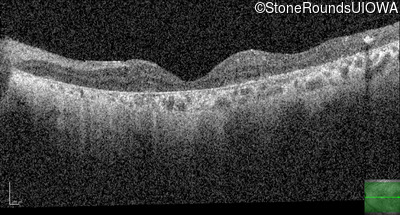

Optical Coherence Tomography - Right - 20/150 sc

Exemplar / OCT Stack

OCT Stack